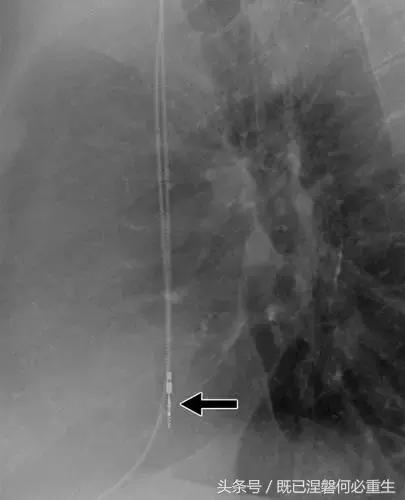

图。 7A 79岁的男性患有电极折断和迁移。

A,初始胸前X线片显示Pacesetter双腔起搏器低于锁骨的心房导线不完全断裂(变薄)(箭头)。

图。 7B 79岁的男性患有电极折断和迁移。

B,大约3年后,电极完全断裂,金属传导碎片(箭头)分离。 远端片段(箭头)已经偏移尾侧,但是因为围绕电极的射线可穿透鞘的约束效应而没有迁移到肺循环中。 引线和中心静脉导管最常见于锁骨和第一肋骨之间断裂,因为它们在臂运动期间被锁骨下肌肉或腱或肋锁韧带压缩[16]。

造成设备故障的最常见的X光检查原因之一是铅断裂。锁骨下静脉经过锁骨下的部位是骨折最常见的位置[16](图7A和7B)。在这个位置的损伤可能发生在导管或导线,并已被描述为锁骨下夹断综合征和锁骨下压溃综合征[16?18]。临床上,骨折的导线通常在患者中产生可以是连续的,间歇的或依赖于患者定位的症状。识别这些状况可能需要挑衅性的动作,例如等长臂锻炼,仰卧或侧向定位或Valsalva。设备检查将显示异常的起搏阻抗(如果绝缘破裂允许导体暴露则减小,如果导体断裂但绝缘完好则增加),感测错误和起搏捕获损失[12]。导线断裂或绝缘损坏可能导致感测或起搏异常。对心律失常的不适当的过感知或欠感应可能导致不适当的治疗,例如抗心动过速起搏和休克治疗,或不适当的抑制治疗。